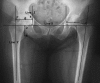

Background: Offset in THA correlates to abductor muscle function, wear, and impingement. Femoral offset after THA is not independent of the cup center of rotation (COR) so hip offset, a combination of femoral offset and change in hip COR, becomes the important measurement.

Questions/purposes: We therefore asked whether hip offset in arthritic hips would correlate with cup COR; whether offset could always be balanced within 6 mm of contralateral normal hips; and whether hip length could also be kept within 6 mm.

Methods: We compared hip offset of arthritic and contralateral normal hips on radiographs in 82 patients (82 hips) who had THA. We used computer navigation in all patients with the aim of reconstructing the hip offset and to compare hip offset change to the quantitative change of the hip COR.

Results: The preoperative radiographic change to equalize the offset ranged from -12 to +21 mm (mean, 1.5); postoperatively the change was 1.4 ± 6.4 mm and was within ± 6 mm in 78 of 82 hips. As COR displaced superiorly from 3 to 6+ mm the offset had to be substantially increased. Only with COR 0-3 mm superior and 0-5 mm medial was offset always within 5 mm.

Conclusions: Hip offset reconstruction was directly related to the position of the hip COR, and navigation allowed quantitative control of offset and hip length.